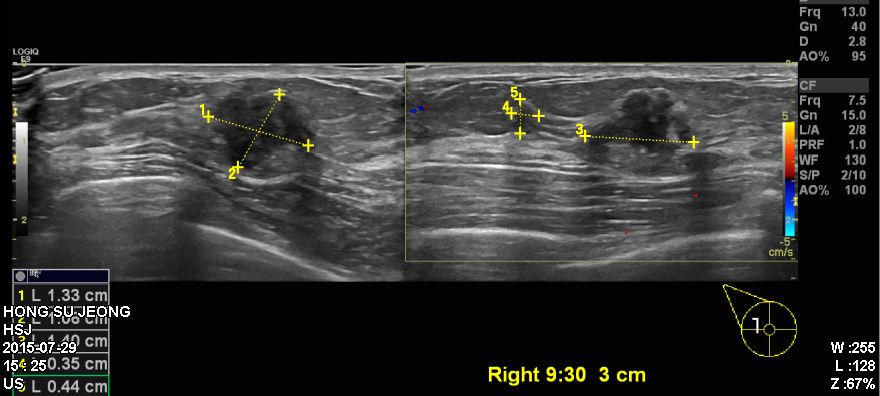

건강검진상 이상 소견으로 정밀검사 위해 내원하신 50대 여성 분으로 본원에서 우측

유방에 9시30분 방향에 3cm 떨어진 곳에 의심스러운 혹 조직검사 시행하여 우측 침윤성

유관암 진단 되었습니다.